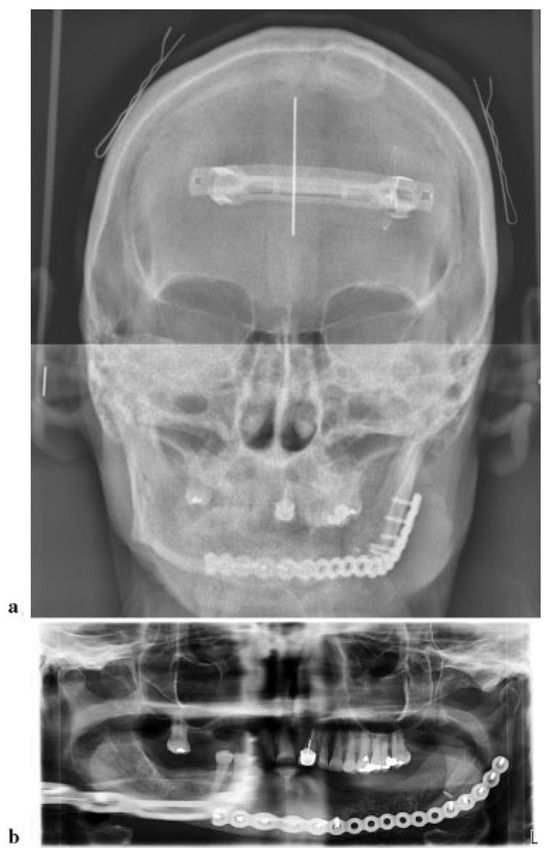

A 72-year-old male patient involved in a roll over tractor accident presented to an outside hospital where he was intubated. Injuries included right upper extremity degloving injury and multiple unstable cervical spine injuries of anterior and posterior columns requiring fusion of C5–T1. It was elected by the spine service not to fuse C2 to allow him rotation of his neck. A CT scan revealed bilateral intracapsular condylar head fractures, a left comminuted mandible fracture, and complex nasal fracture (Figure 1a–c). Additionally, he had a transverse body fracture of C2 and C5 through T1. The patient was transferred to the University of Kentucky for further management.

Figure 1. (a) 3D preoperative CT reconstruction of the injury from a three-fourths view. Note the intracapsular head fracture on the left. (b) Submental vertex view showing displacement and comminution. (c) Axial CT showing comminution. As the maxillary fracture was minimally displaced, the authors believed that any discrepancies would be resolved with an eventual prosthesis.